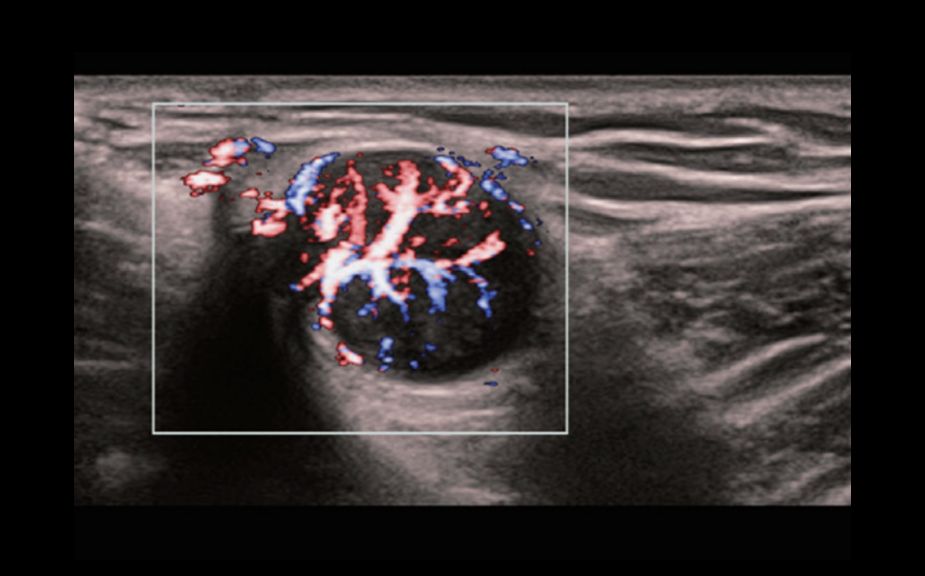

A Novel Approach of Vascular Hemodynamics: V Flow

Kolorowe wektory wskazuj? szybko?? i kierunek przep?ywu kom├│rek krwi. Dzi?ki wysokiej cz?stotliwo?ci od?wie?ania obrazu, V Flow zapewnia niezwykle ?yw?, dok?adn? i niezale?n? od k?ta nachylenia bramki dopplerowskiej wizualizacj? z?o?onych przep?yw├│w hemodynamicznych w naczyniach.

V Flow

A Novel Approach of Vascular Hemodynamics: V Flow

Kolorowe wektory wskazuj? szybko?? i kierunek przep?ywu kom├│rek krwi. Dzi?ki wysokiej cz?stotliwo?ci od?wie?ania obrazu, V Flow zapewnia niezwykle ?yw?, dok?adn? i niezale?n? od k?ta nachylenia bramki dopplerowskiej wizualizacj? z?o?onych przep?yw├│w hemodynamicznych w naczyniach.

V Flow